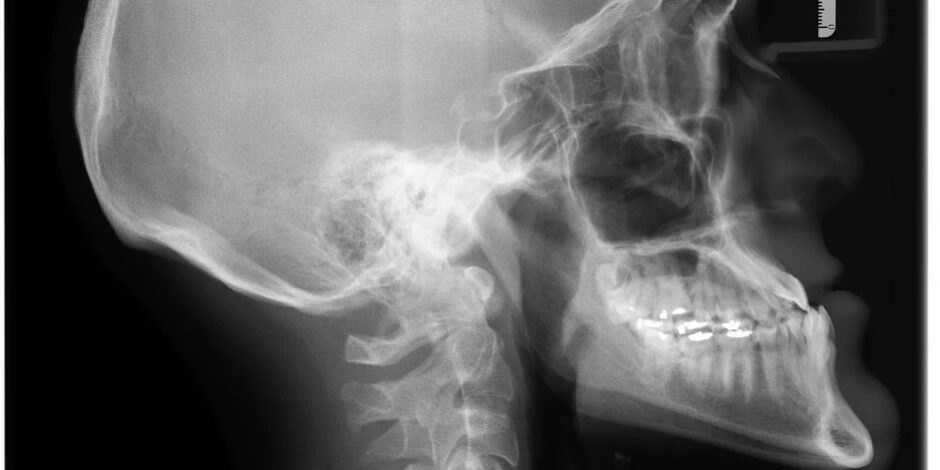

Underbites are overly prominent lower front teeth, that can also be referred to as reverse bite, under bite, or Class III malocclusion, and may be due to multiple causes (Watkinson, S et al., 2013).

In some cases, the maxilla (upper jaw part of the skull) can be too far back or the mandible (lower jaw) is too far forward, or both. Also, if either the upper or lower front teeth are tipped back or forwards respectively, or both (Watkinson, S et al., 2013), underbites can result.